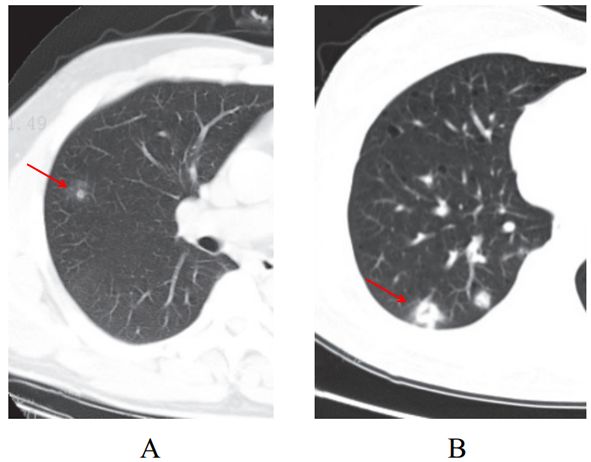

(五)结节伴晕征

部分案例实性结节病灶周围出现磨玻璃密度影,边缘模糊,称为晕征。

根据既往病理学机制提示,病灶中心实变影为肺泡腔内聚集大量富细胞渗出液,显示为实性密度灶;其周围肺泡亦见渗出,包含炎症细胞、蛋白质、纤维素等,形成“膜状物”,或形成磨玻璃密度阴影(图 2-5)。

图 2-5 结节伴晕征(A和B)